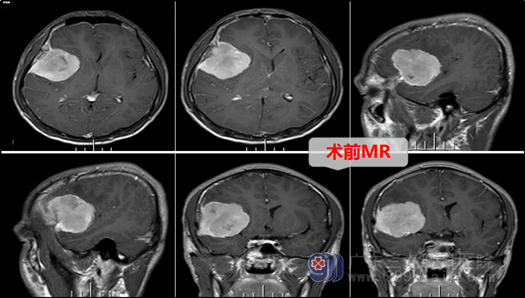

外十科主任欧阳辉教授接诊了患者,结合磁共振检查结果,欧阳主任给出诊断:1、右侧额部占位性病变:考虑脑膜瘤,2、继发性癫痫。

欧阳辉主任解析:这位小伙子患的是额部脑膜瘤,就是位于额叶表面从脑膜上长出并压迫额叶脑组织的脑膜瘤,这是一种良性的肿瘤,脑膜瘤主要是呈膨胀性的生长,一般边界清楚,形状规则, 通过CT、磁共振检查大多就能够明确诊断,MR增强影像上除肿瘤外多可以看到典型的脑膜尾征。肿瘤逐渐长大,可以压迫额叶,导致出现头疼、癫痫等症状,主要表现为前额的胀痛和太阳穴的胀痛,有时对于脑组织的压迫严重,刺激脑皮层也可以引起癫痫发作等情况,脑膜瘤的治疗主要是以手术切除为主。

经过欧阳辉主任团队的讨论和并征得患者家属的同意后,决定做手术切除。外十科团队于11月29日在全麻下行右侧额部脑膜瘤切除术+硬脑膜修补+颅骨成形术。手术非常成功,肿瘤被完整摘除。